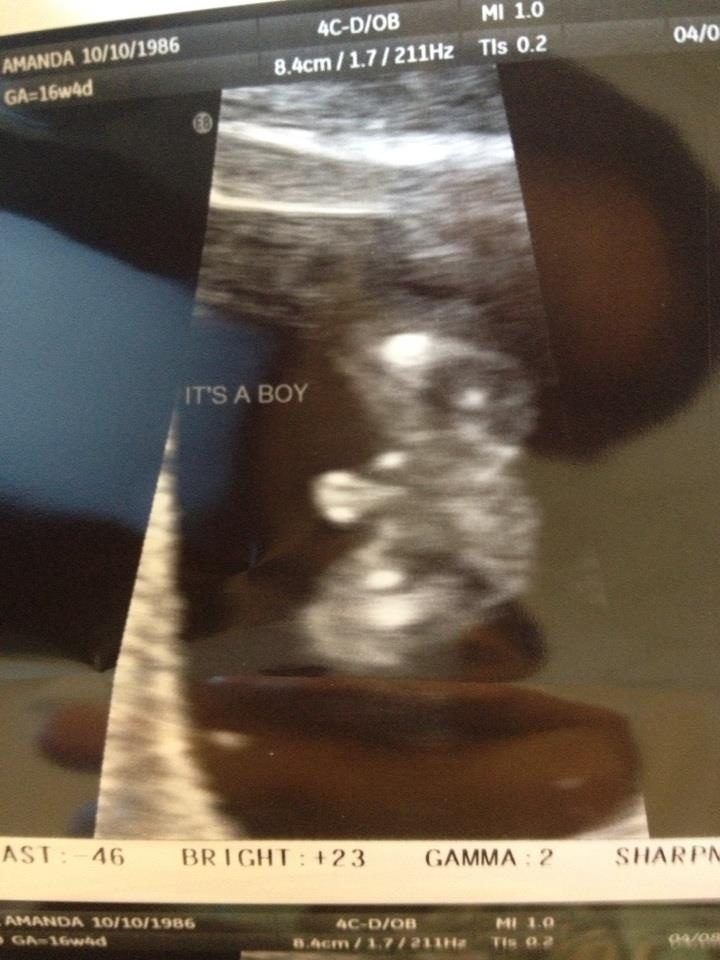

I'm so happy to finally have my little boy. I can't wait to meet him. Attachment 10516